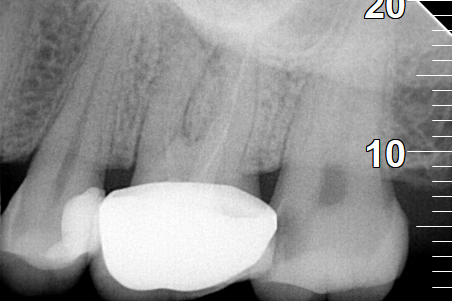

ΜΕΤΑ

ΠΡΙΝ